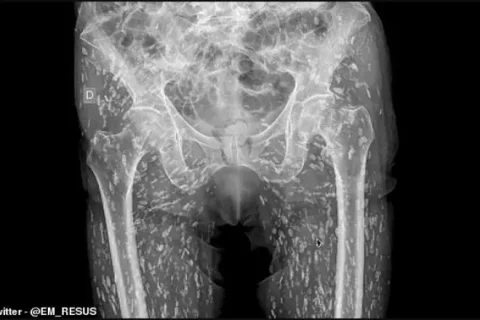

Τρομακτική ακτινογραφία: Σώμα ασθενούς είχε γεμίσει σκουλίκια από το παράσιτο ταινία

Μία απίστευτη περιπέτεια υγείας έζησε ένας ασθενής από τη Φλόριντα, αφού έφαγε...